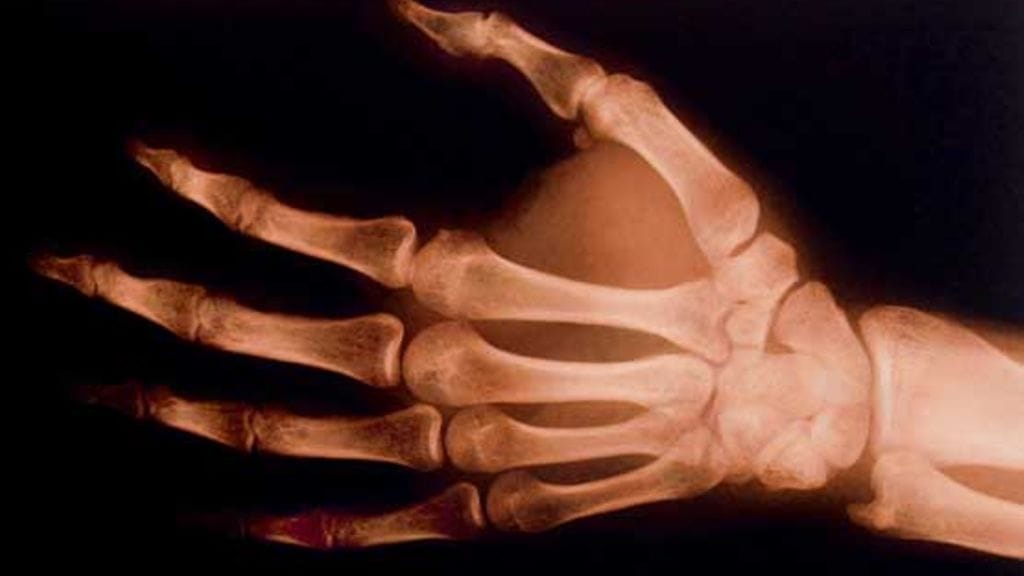

− Kädestä otettiin röntgenkuva. Lääkäri totesi, että veneluussa on murtuma, joka vaatii kipsin, Vivan kertoo.

Sairaalassa ortopedi tarkasteli vanhaa röntgenkuvaa ihmeissään. Kolmioluussa oli kenties pieni hiusmurtuma, mutta aiemmin murtuneeksi diagnosoitu veneluu oli täysin kunnossa.